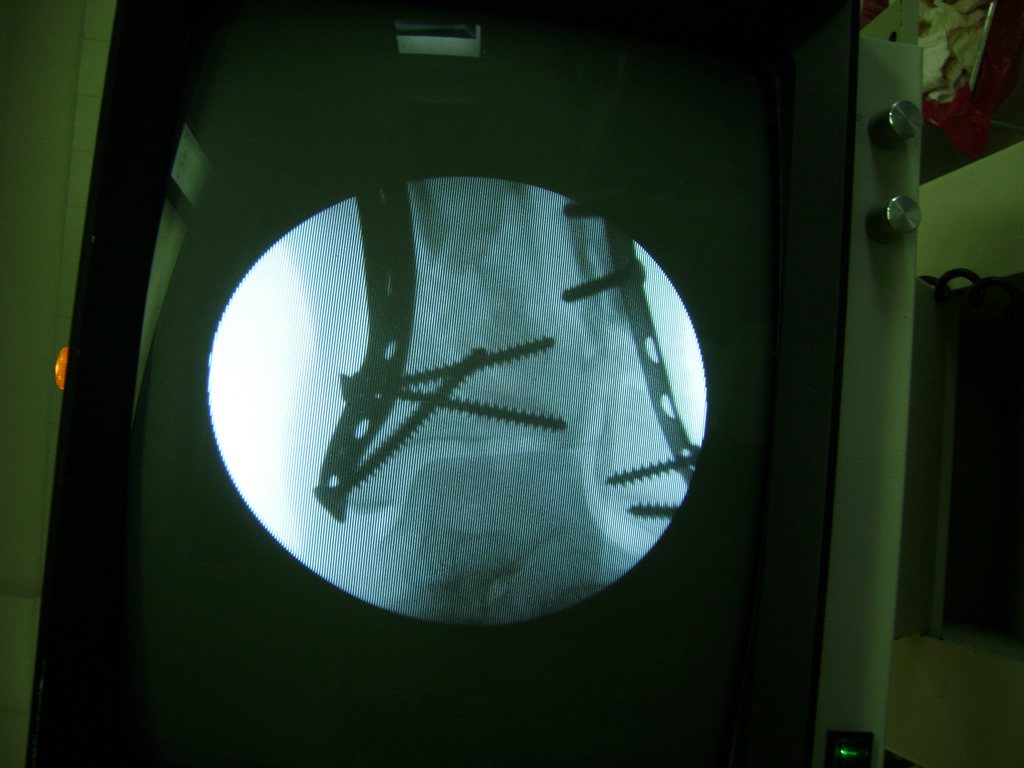

Cuando se necesita cirugía, es probable que esta implique el uso de clavijas de metal, tornillos o placas para sostener los huesos en su lugar mientras la fractura se consolida. Los elementos de soporte pueden ser temporales o permanentes.